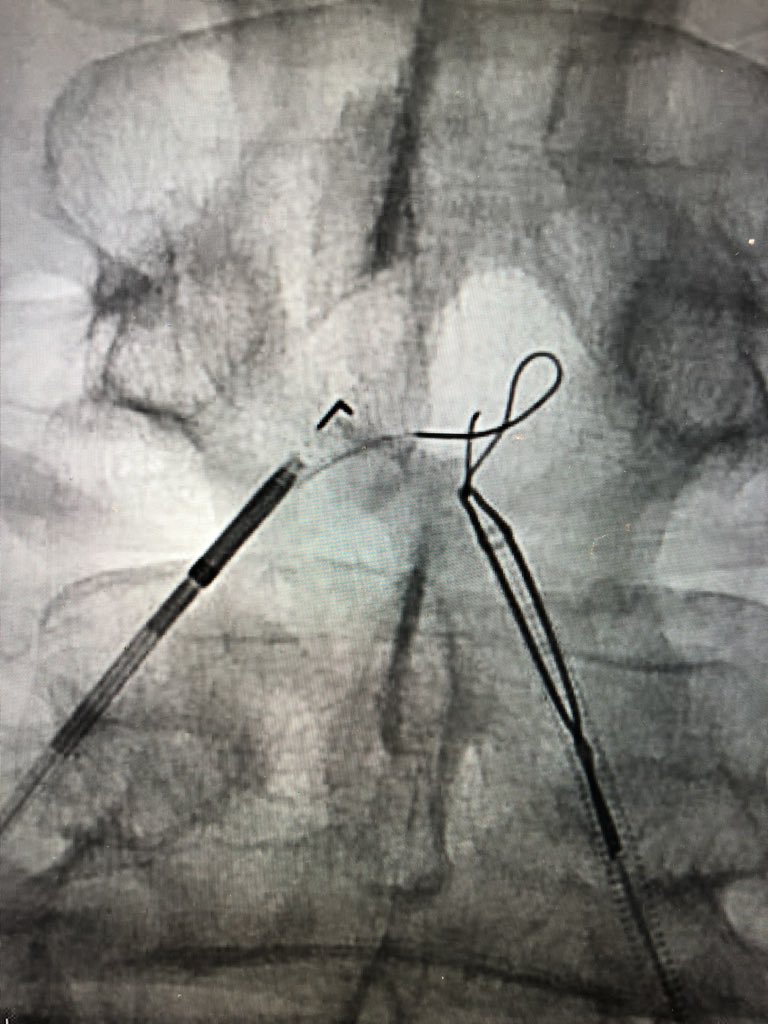

The best example of CTOP IV I've seen clinically. Know the techniques! Procedures failed by others become routine when you understand the pathology. #CLIFighters #MyLegMyLife #Can'tCTOPWon'tCTOP @SOBE_Vascular @kmadass @SDhandMD @Mustapja @FadiSaab17 @LessneVIR @SIR_ECS @SIRRFS